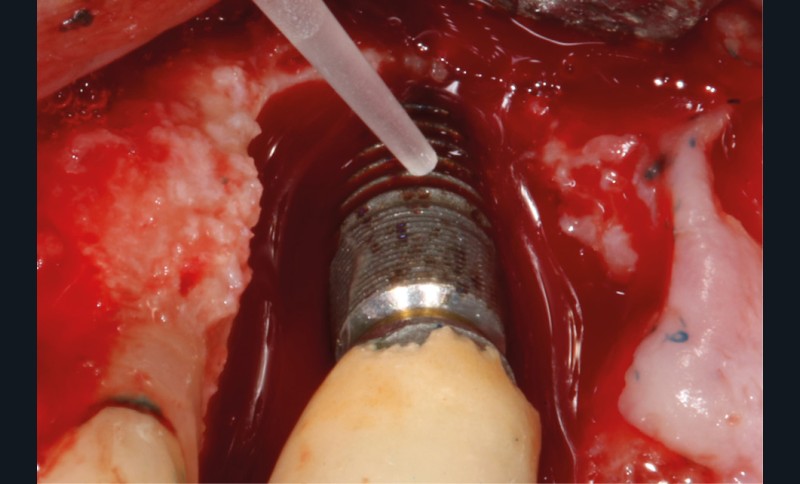

L’implant

- Site 23

- Mis en place il y a 12 ans

- Parmi ces longueurs d’onde, deux lasers (Er-YAG et Diode) sont intéressants dans le traitement de la péri-implantite :

– Le laser Er-YAG, utilisé pour le nettoyage, est un laser avec un milieu actif composé d’yttrium, d’aluminium et de grenat dopé à l’erbium. Avec une longueur d’onde de 2 940 nm situé dans l’infrarouge, le laser Er-YAG est un laser à haute énergie, dont la lumière est absorbée dans l’eau et dans l’hydroxyapatite et qui ne pénètre pas profondément. Ceci permet de couper des tissus mous et des tissus durs, mais également de désorganiser le biofilm bactérie.